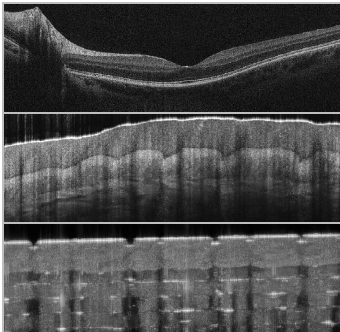

同时,Cobra-S 800采用独特的Cobra-S长距离成像,在保持分辨率的情况下,将成像深度增加了一倍。特别适用于眼科,引导手术,以及激光焊接深度监测。

▲上图为麻省理工学院的James Fujimoto 提供的视网膜图像,使用Cobra-S进行高分辨率、高速扫描可以对组织和材料样本在不求平均的情况下进行宽场成像。